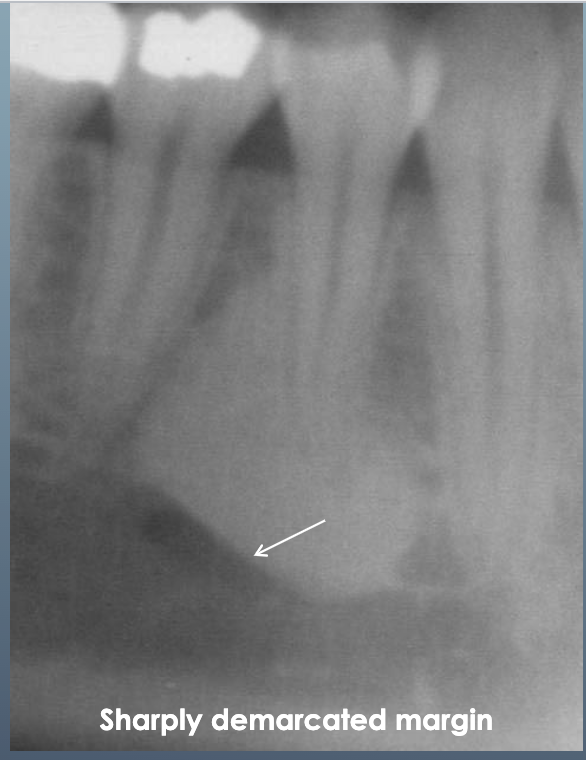

13

Q

What’s ths?

A

IDIOPATHIC OSTEOSCLEROSIS